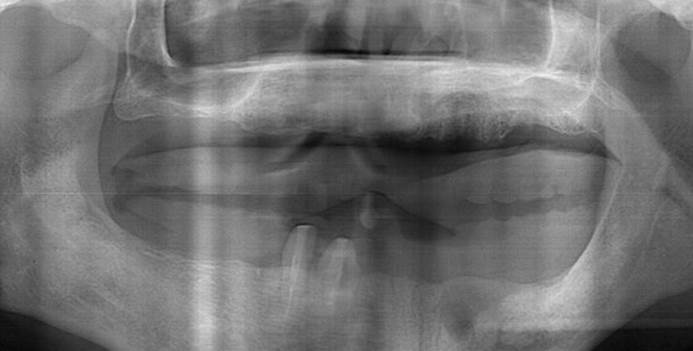

How can primary stability be increased?

Primary stability is especially important in the case of poor quality bone. The instability of dental implants results in fibrous encapsulation and failed osseointegration (Lioubavina-Hack, et al. 2006). One method for increasing primary stability is modifying the surgical technique for implant placement. Studies have reported that the undersized surgical technique, which uses a final drill diameter smaller than the diameter of the implant, results in a higher primary stability when compared with the press-fit technique (Tabassum, et al. 2009, Tabassum, et al. 2010a).

Another method increasing the primary stability is to change the implant design, such as the shape of the implant body and thread, length, and diameter. Various thread designs for taper implants and other dental implant designs have already been reported to effect the primary stability. Taper implants also show a higher primary stability than cylindrical implants (Kim, et al. 2009, Sakoh, et al. 2006, Wilmes, et al. 2008).

Meanwhile, dental implants with a long length or wide diameter show a significantly increased insertion torque (Kim,et al. 2009, Wilmes, et al. 2008). Plus, dental implants without self-tapping blades have a higher primary stability than implants with self-tapping blades (Kim et al. 2011).